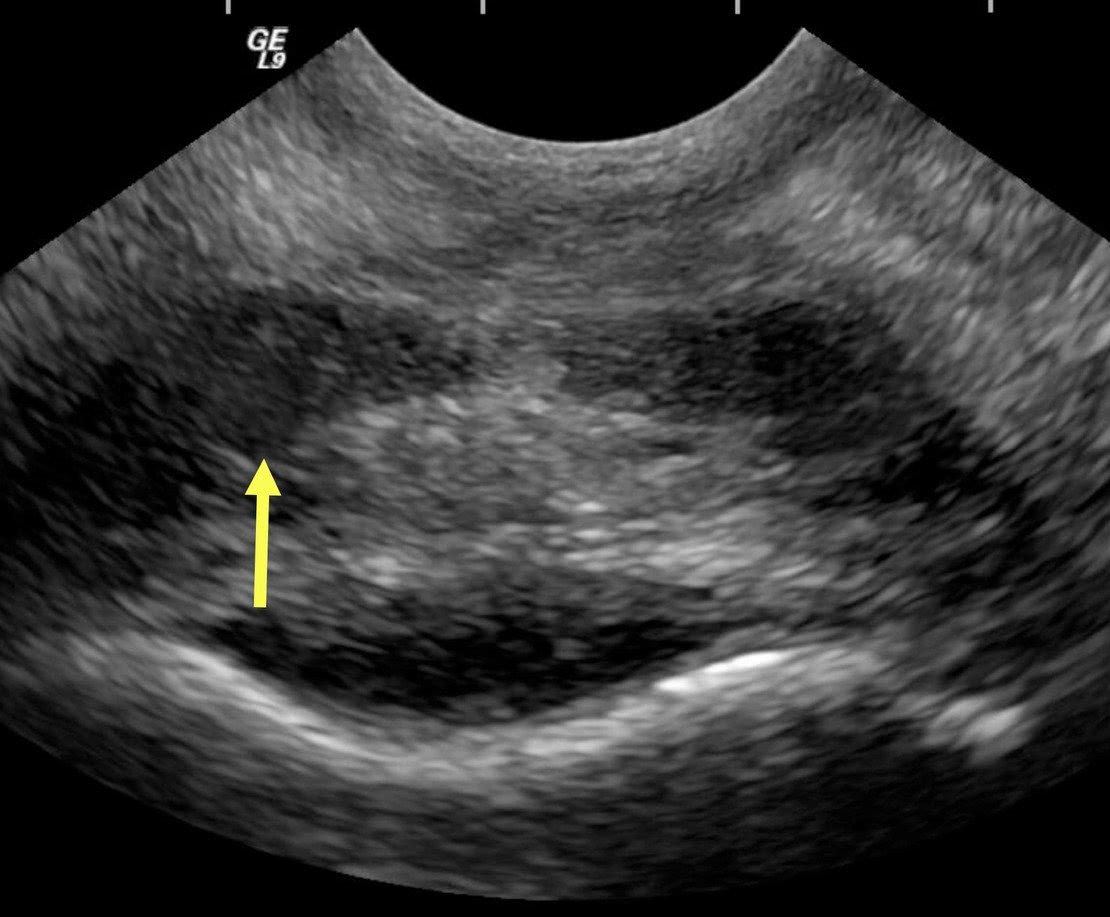

Ультразвуковое исследование

Работа врача УЗИ считается достаточно «непыльной», так как этому специалисту не требуется совершать обходы и объезды пациентов, а также почти не приходится иметь дело с неприятными физиологическими проявлениями. Основной рабочий инструмент узиста – специализированное оборудование и компьютер, поэтому врачу этой специальности приходится сталкиваться со всеми теми недостатками, которые влечёт за собой длительная работа за компьютером. Это нагрузка на зрение, сидячая работа с недостатком физической активности, возможные боли в руках и спине, необходимость пропускать через себя большой объём информации. Также в случае отсутствия медсестры врачам УЗИ приходится самим писать заключения, соблюдая все правила ведения медицинской документации. Определённую психологическую нагрузку несёт и взаимодействие с пациентами.